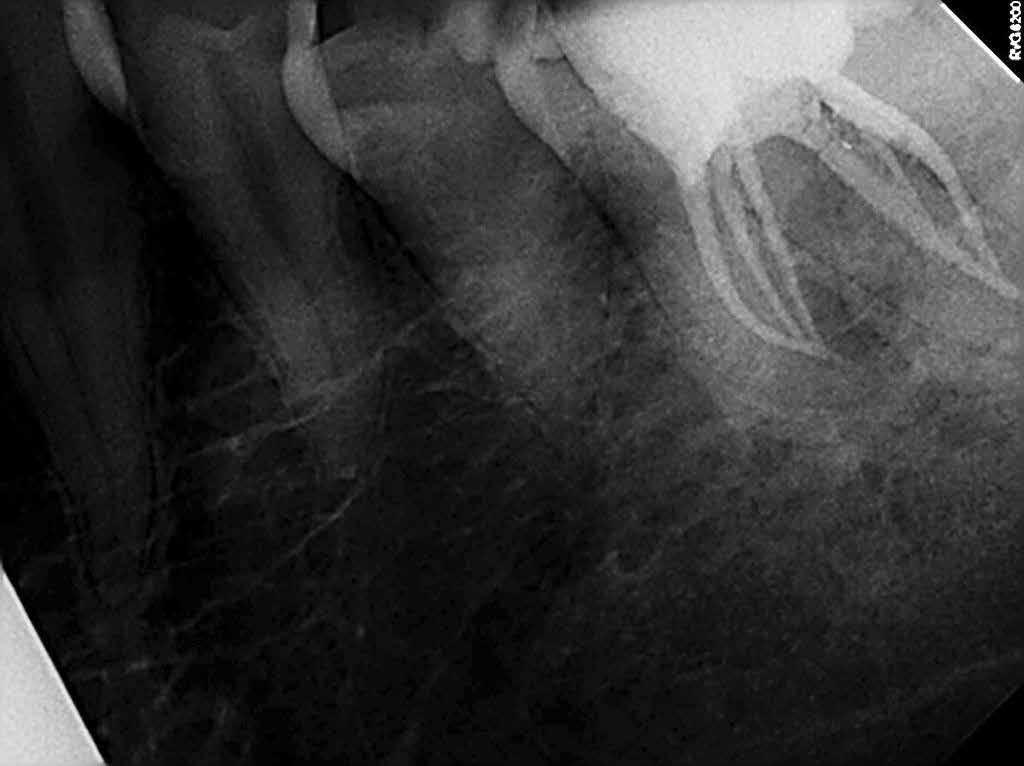

A kezdeti konzultáció során az LL6 nem reagált az Endo-Frost (COLTENE) és az Electric Pulp testerrel végzett érzékenységi vizsgálatokra, és ütögetésre érzékenynek bizonyult. Bukkálisan a lágyrészekhez kapcsolódó fisztulát észleltek, és tapintásra némi érzékenységet, míg a fogak mozgékonysága a normális határokon belül volt. A műtét előtt készült periapikális röntgenfelvételen az LL6 gyökereihez kapcsolódó periradikuláris röntgenfelvételek voltak láthatóak (1. ábra).

Ebben az esetben hat csatornát azonosítottak és kezeltek. Általában az alsó állkapocs első őrlőfogainak három-négy csatornája van.[i] Azt is feltételezték, hogy az első alsó őrlőfogak 3%-ának lehet egy harmadik meziális vagy disztális csatornája.[ii] Ebben az esetben egy harmadik csatornát azonosítottak és kezeltek mind meziálisan, mind disztálisan, és az utóbbi lelet előfordulása egyetlen fogban rendkívül ritka, mindössze három esetről szóló közlemény jelent meg [iii], [iv], [v].

Az LL6 végleges obturálását folyamatos kondenzációs hullámtechnikával végeztük, és a hozzáférési üreget a COLTENE által gyártott, több árnyalatú nano hibrid kompozittal, aMIRIS®2-vel zártuk le (2–4. ábra).